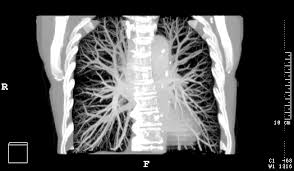

How To Detect Lung Cancer Ct Scan : Serial Chest Ct Scans A At The Time Of The Small Cell Lung Cancer Download Scientific Diagram / This provides a series of images from many different angles.. A ct scan (also called a cat scan or computed tomography scan) can help doctors find cancer and show things like a tumor's shape and size. This lung cancer awareness month learn how future processing is able to detect lung cancer from ct scans with the help of ai. The computer puts them together to make a 3 dimensional (3d) image. How does a ct or cat scan work? It can also show the size, shape, and position of any lung tumors and can help find enlarged lymph nodes that might contain cancer that has spread.

Ct screening for lung cancer has only been studied in people at high risk of lung cancer — those with a long smoking history and who are 55 and older. Because ct scans can detect even very small nodules in the lungs, ldct of the chest is especially effective for diagnosing lung cancer at its earliest, most health insurance companies and medicare will only cover the cost of an ldct scan to screen for lung cancer in patients who meet certain criteria. A ct scan can help to diagnose lung cancer. Lung cancer is the world's deadliest cancer and it takes countless lives each year. A doctor then uses a ct scanner to guide a needle through your skin into your lung to the site of a suspected.

It's also important to follow recommended screening guidelines, which can help detect certain cancers early. Ct (or cat) stands for computed (axial) tomography. Pet and nuclear medicine scans. What to expect when undergoing this test. Low dose ct scan (low dose computed tomography scan). Abstract—lung nodules are potential manifestations of lung cancer, and their early detection facilitates early treatment and improves patient's for this reason, cad systems for lung cancer have been proposed in several studies. Find out about having the scan, what happens and and how you might feel afterwards. Lung cancer screening ct protocols version 5.1 13 september 2019 lung cancer screening. How often should you have a ct scan for lung cancer? The computer puts them together to make a 3 dimensional (3d) image. This provides a series of images from many different angles. It takes pictures from different angles. Ct scans can detect bone and joint problems, like complex bone fractures and tumors.

Understanding Your Chest Ct Scan Pet Scan For Lung Cancer Detection from www.docpanel.com As a ct scan detects abnormal tissue, it is useful for planning areas for radiotherapy and biopsies. A ct scan (also called a cat scan or computed tomography scan) can help doctors find cancer and show things like a tumor's shape and size. Ct (or cat) stands for computed (axial) tomography. Lung cancer detection using ct scan. Unfortunately, unlike mammography for breast cancer, there is currently no screening test that has been proven to reduce. What is ct lung cancer screening? A ct scan can help to diagnose lung cancer. This lung cancer awareness month learn how future processing is able to detect lung cancer from ct scans with the help of ai.